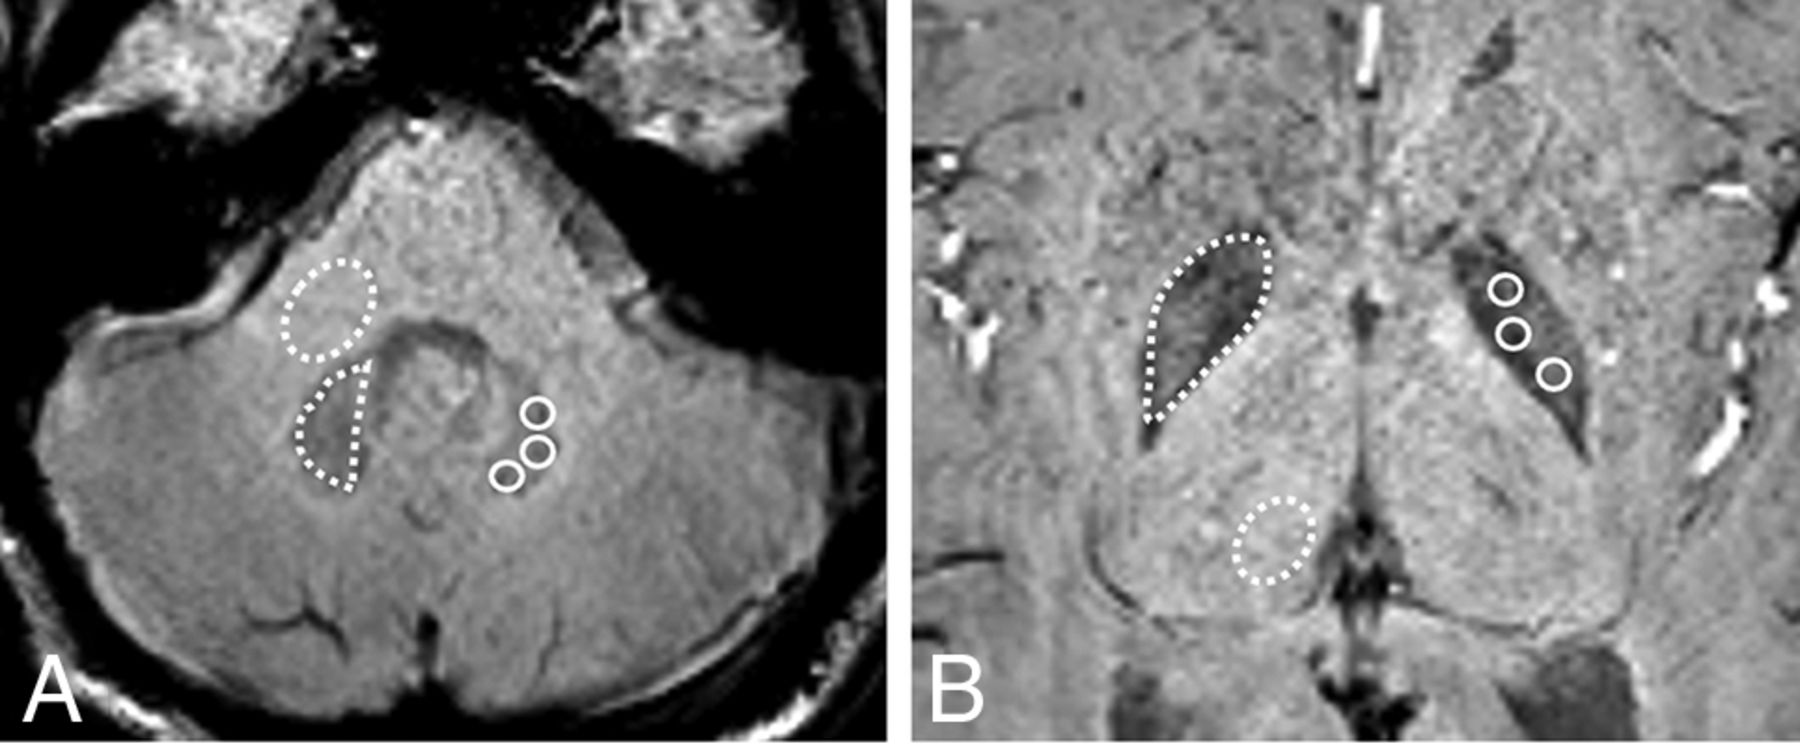

The DN-to-MCP ratios for SWImean and SWImin were lower in those with only linear GBCA administration (SWImean, 0.898 [SD, 0.056]; SWImin, 0.835 [SD, 0.073]) than in both the macrocyclic GBCA group (SWImean, 0.992 [SD, 0.061]; SWImin, 0.928 [SD, 0.064]) and the control group (SWImean, 0.985 [SD, 0.032]; SWImin, 0.925 [SD, 0.037]) (adjusted P value < .001). No significant differences in the DN-to-MCP ratio for SWImean and SWImin were noted between the macrocyclic GBCA group and the control group (P = .595 and .829, respectively). The mean DN-to-MCP ratios on T1WI in the linear GBCA group (0.986 [SD, 0.073]) were also higher than those in the non‐GBCA group (0.926 [SD, 0.042]) and the macrocyclic GBCA group (0.930 [SD, 0.043]) (adjusted P value < .001) (Fig 2). A moderate negative correlation was identified between the DN-to-MCP ratio for SWImean and SWImin and the number of linear GBCA administrations (SWImean, r = –0.43 and P = .005; SWImin, r = –0.38 and P = .011) (Fig 3).

Scatterplot of the DN-to-MCP ratios for SWImean, SWImin, and T1WI versus the number of intravenous linear GBCA administrations, with linear regression lines for each group.

The GP-to-Th ratios for SWImean and SWImin were lower in those with only linear GBCA administration (SWImean, 0.765 [SD, 0.041]; SWImin, 0.751 [SD, 0.038]) than in both the macrocyclic GBCA group (SWImean, 0.804 [SD, 0.047]; SWImin, 0.793 [SD, 0.045]) and the control group (SWImean, 0.857 [SD, 0.052]; SWImin, 0.841 [SD, 0.048]) (adjusted P value < .001). No significant differences of the GP-to-Th ratio for SWImean and SWImin were noted between the macrocyclic GBCA group and the control group (P = .503 and 0.778, respectively). Mean GP-to-Th ratios on T1WI in the linear GBCA group (1.001 [SD, 0.072]) were also higher than in the non‐GBCA group (0.953 [SD, 0.047]) and the macrocyclic GBCA group (0.958 [SD, 0.049]) (adjusted P value < .001). A moderate negative correlation was identified between the GP-to-Th ratio for SWImean and SWImin and the number of linear GBCA administrations (SWImean, r = –0.39, P = .009; SWImin, r = –0.33, P = .017).The Pearson correlation coefficient revealed no significant correlation between SWI/T1WI–derived values and the mean time interval among MR imaging, total GBCA dose, and age (all P > .05). There was no significant difference in the SWI/T1WI–derived SI ratios regarding sex, intrinsic disease, and a history of radiation or chemotherapy (all P > .05). Multivariate linear regression analyses derived from univariate analysis demonstrated that SWImean and SWImin ratios were associated with the number of linear GBCA administrations (adjusted R2 for the model = 0.185) (SWImean; β = –0.022, P = .015; SWImin; β = –0.026, P = .028). Additionally, no significant correlation was noted between SWI-derived values and age in the control groups (SWImean: r = –0.14, P = .15; SWImin: r = –0.11, P = .24).